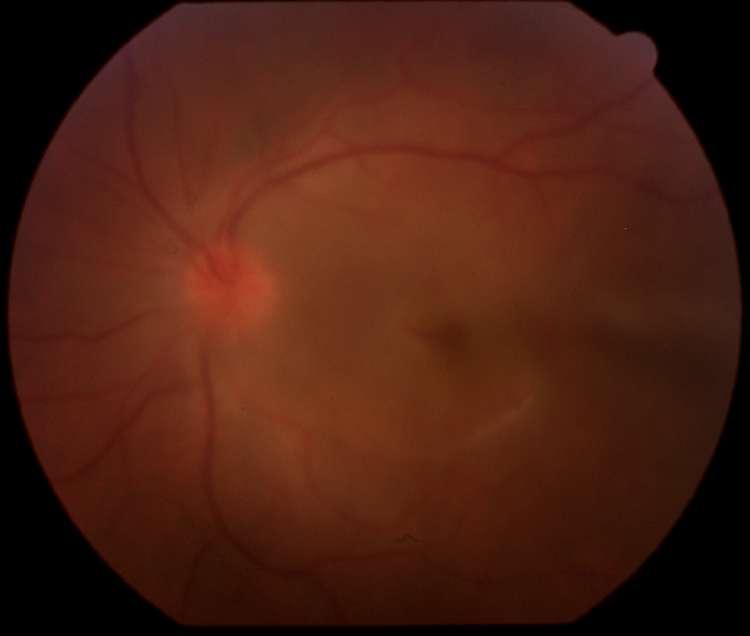

INTRAOCULAR

C D

2.E. HERIDA PENETRANTE OCULAR + CATARATA TRAUMÁTICA

Caso aportado por Dr. Matías Ramirez y Dra. María José Vergara

üPaciente 35 años le cae cuerpo extraño metálico al ojo, el cual atraviesa espesor corneal, la cápsula anterior, el cristalino, cápsula posterior

AüQuemosis conjuntival en 360º

Catarata traumática

üRuptura capsula anterior

üMasas libres

ü Herida penetrante corneal

üAumento de grosor corneal secundario a edema corneal